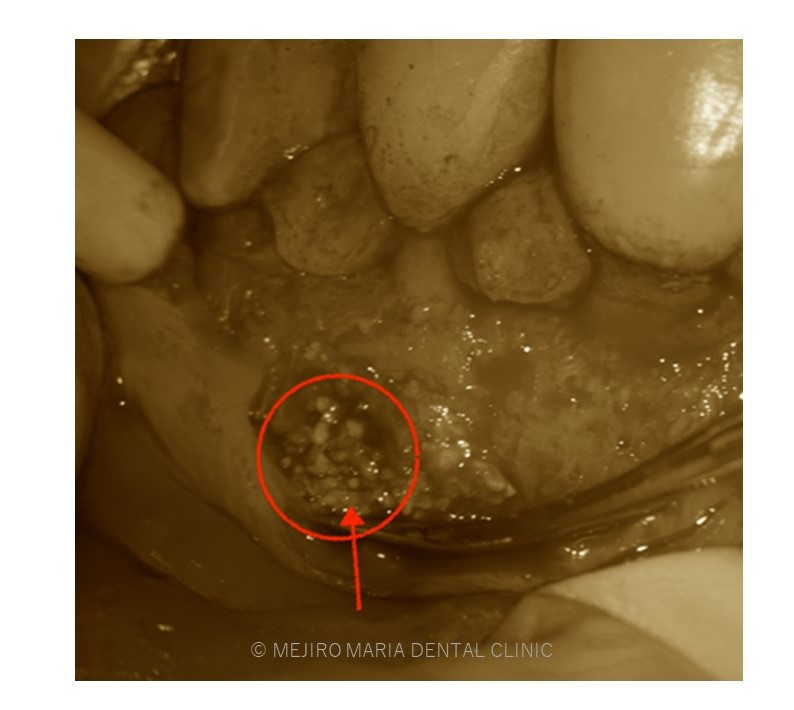

でのリカバリー_感染した人工骨の画像.jpg)

でのリカバリー_治療前の口腔内画像と感染した人工骨の画像-1.jpg)

今回の症例は、他院にて歯根端切除術を行った根尖部(歯の根の先)に充填された人工骨の感染が原因と考えられます。

万が一、歯根端切除術が失敗した場合、人工骨の感染はより事態を悪化させることになります。

歯根端切除術後は術後の透過像で治癒を確認することが重要であり、感染が除去できていれば骨は患者自身の力で自然に再生を行うことになるので、人工骨を充填することはリスクが高い行為であると考えます。